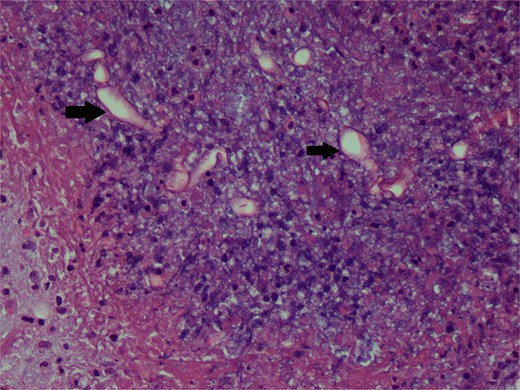

The whole arm was edematous, with evident flexion contracture at the elbow joint. The median nerve was intact. Ulnar and radial could not be assessed due to excessive edema. Her histopathology reports showed chronic granulomatous inflammation and invasive fungal infection, likely mucormycosis, and were negative for malignancy (Figs 2 and 3).

Hematoxylin and eosin stain photomicrograph showing fungal hyphae.